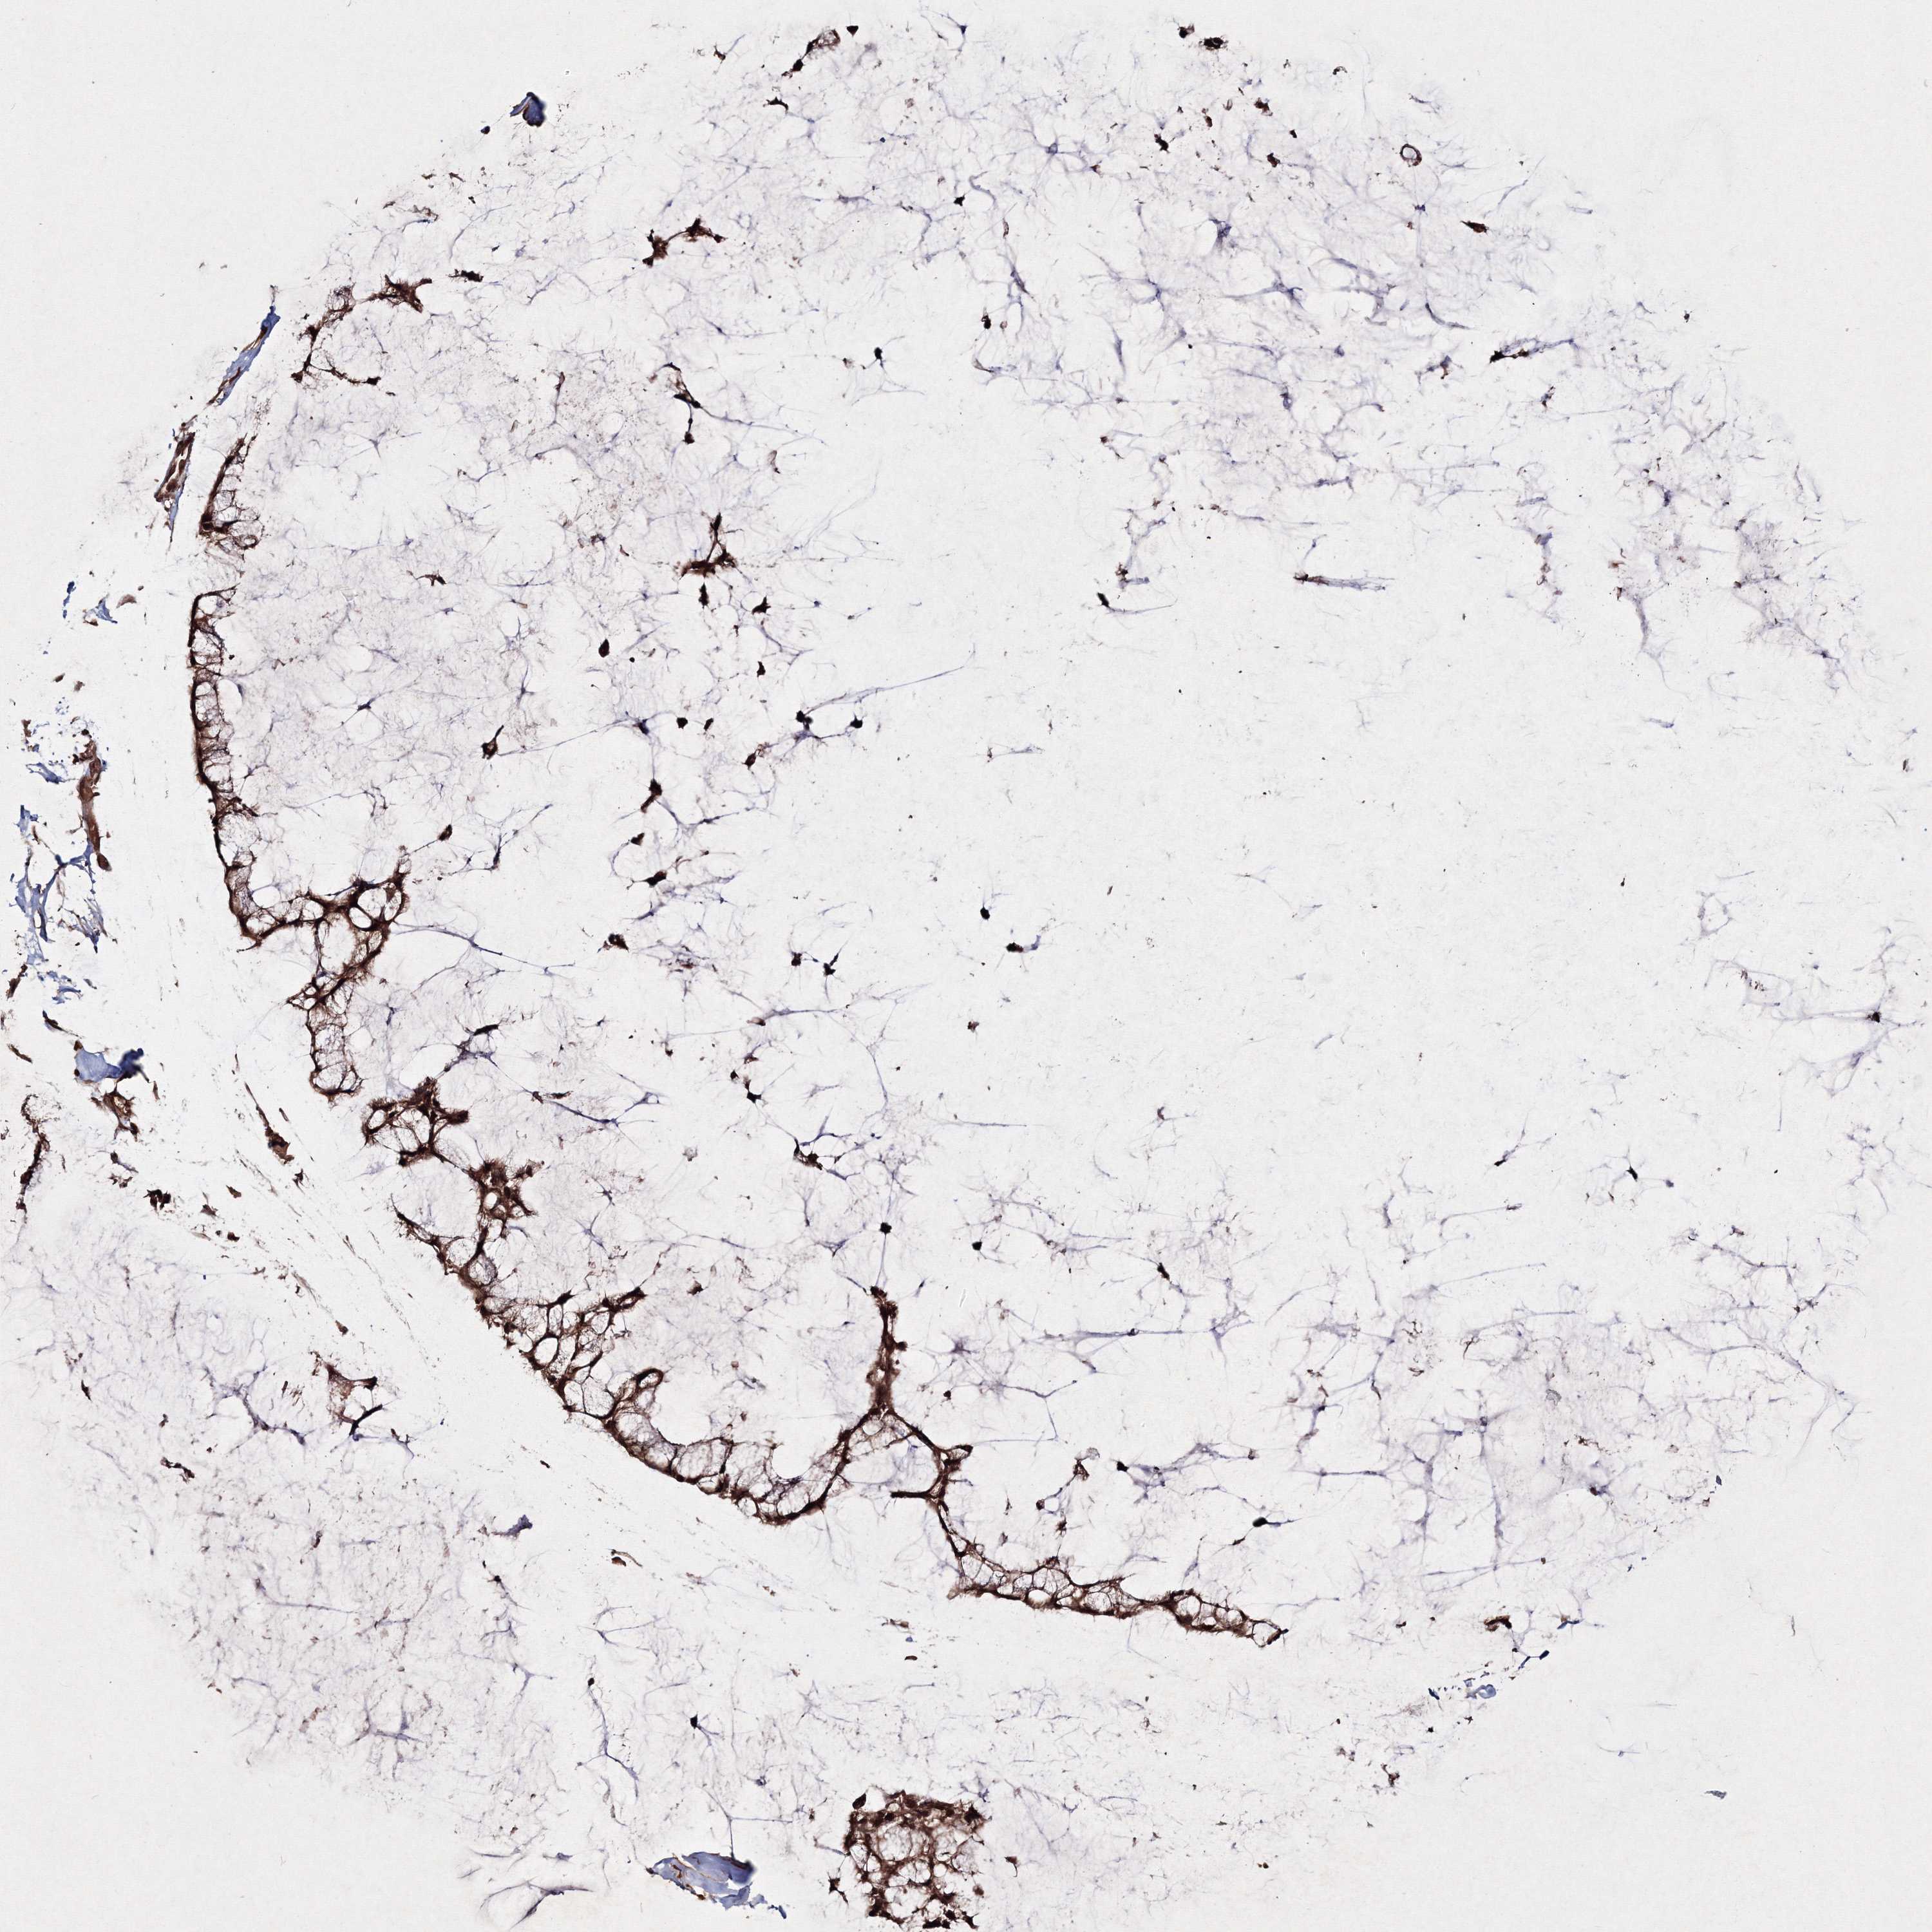

OVARIAN CANCER - Protein expressioni

A mouse-over function shows sample information and annotation data. Click on an image to view it in a full screen mode. Samples can be filtered based on level of antibody staining by selecting one or several of the following categories: high, medium, low and not detected. The assay and annotation is described here.

Note that samples used for immunohistochemistry by the Human Protein Atlas do not correspond to samples in the TCGA dataset.

Antibody stainingi

Antibody staining in the annotated cell types in the current human tissue is reported as not detected, low, medium, or high, based on conventional immunohistochemistry profiling in selected tissues. This score is based on the combination of the staining intensity and fraction of stained cells.

Each image is clickable and will lead to virtual microscopy that enables deeper exploration of all samples and also displays staining intensity scores, fraction scores and subcellular localization as well as patient and tissue information for each sample.

Antibody HPA032141

Antibody HPA032142

Antibody CAB032689

Staining

High

Medium

Low

Not detected

Intensity

Strong

Moderate

Weak

Negative

Quantity

>75%

75%-25%

<25%

None

Location

Nuclear

Cytoplasmic/membranous

Cytoplasmic/membranous,nuclear

Cystadenocarcinoma, serous, NOS

Carcinoma, endometroid

Cystadenocarcinoma, mucinous, NOS

Carcinoma, NOS